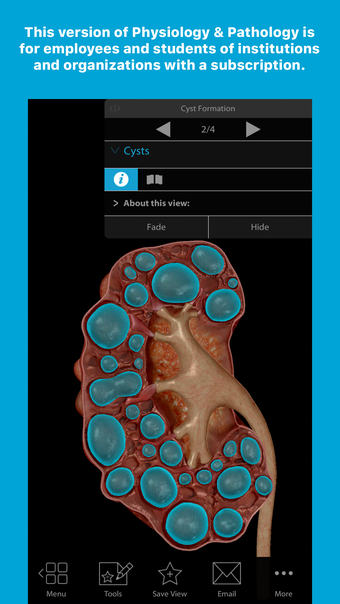

PP-Abonnement ist eine iPhone-App, die von VBLEARNING LLC entwickelt wurde. Sie fällt in die Kategorie Bildung & Nachschlagewerke, speziell im Bereich Medizin. Diese Version von Physiologie & Pathologie ist für Mitarbeiter und Studenten von Institutionen und Organisationen mit einem Abonnement konzipiert.

Neben der Synchronisierung von Gesundheitsdaten bietet PP-Abonnement eine umfassende Erforschung von Physiologie & Pathologie. Benutzer können in die Feinheiten des menschlichen Körpers eintauchen und verschiedene physiologische Prozesse und pathologische Zustände kennenlernen. Die App bietet detaillierte Informationen, interaktive Visualisierungen und Quizfragen, um das Lernerlebnis zu verbessern.